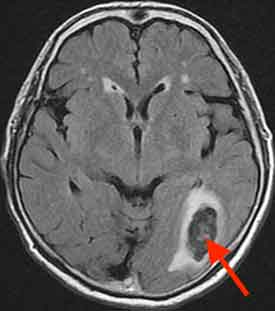

50代の女性の症例です。 元々視野が欠ける閃輝暗点を伴う片頭痛がありました。ある日、視野が欠けて見えるようになりました。ところが、かつてのように頭痛は出現しませんでした。頭痛がなかったため心配になり、翌日横浜脳神経内科を受診しました。

念のためMRI検査を行いました。

左の後頭葉に脳出血を起こしており、救急車で入院していただきました。後頭葉は視覚に関係する場所です。つまり、出血により後頭葉が障害されて生じた視野狭窄と思われました。